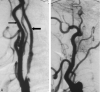

Background and purpose: Two large trials indicated that endarterectomy was less beneficial for symptomatic patients with internal carotid artery (ICA) near occlusion than for patients who had severe stenosis without near occlusion. Near occlusions complicate ratio calculations of ICA stenosis and require attention to detail for identification. The goal is to provide diagnostic criteria, illustrate identifying features, estimate accuracy of identification, and assess prognosis for patients with near occlusion.

Methods: We re-reviewed 1216 patients with severe (> or =70%) stenosis on angiography in the North American Symptomatic Carotid Endarterectomy Trial and European Carotid Surgery Trial. One of 5 (n = 262) had 2 or more criteria for near occlusion: (1) delayed cranial arrival of ICA contrast compared with external carotid artery (ECA); (2) intracranial collaterals seen as cross-filling of contralateral vessels or ipsilateral contrast dilution; (3) obvious diameter reduction of ICA compared with opposite ICA; or (4) ICA diameter reduction compared with ipsilateral ECA.

Results: Interrater agreement, sensitivity, and specificity were excellent (0.88, 90.6%, and 93.8%, respectively). By intention to treat, 3-year risks of ipsilateral stroke for medically treated patients with near occlusion was 15.1% versus 10.9% for surgically treated (absolute risk reduction [ARR] = 4.2%; P value = .33). Patients who continued to receive treatment in the medical arm for the trial's duration had a 3-year risk of 18.3% (ARR = 7.4%; P value = .13). Medically treated patients with severe stenosis but without near occlusion had a 3-year risk of 26.0% versus surgically treated of 8.2% (ARR = 17.8%; P value < .001).